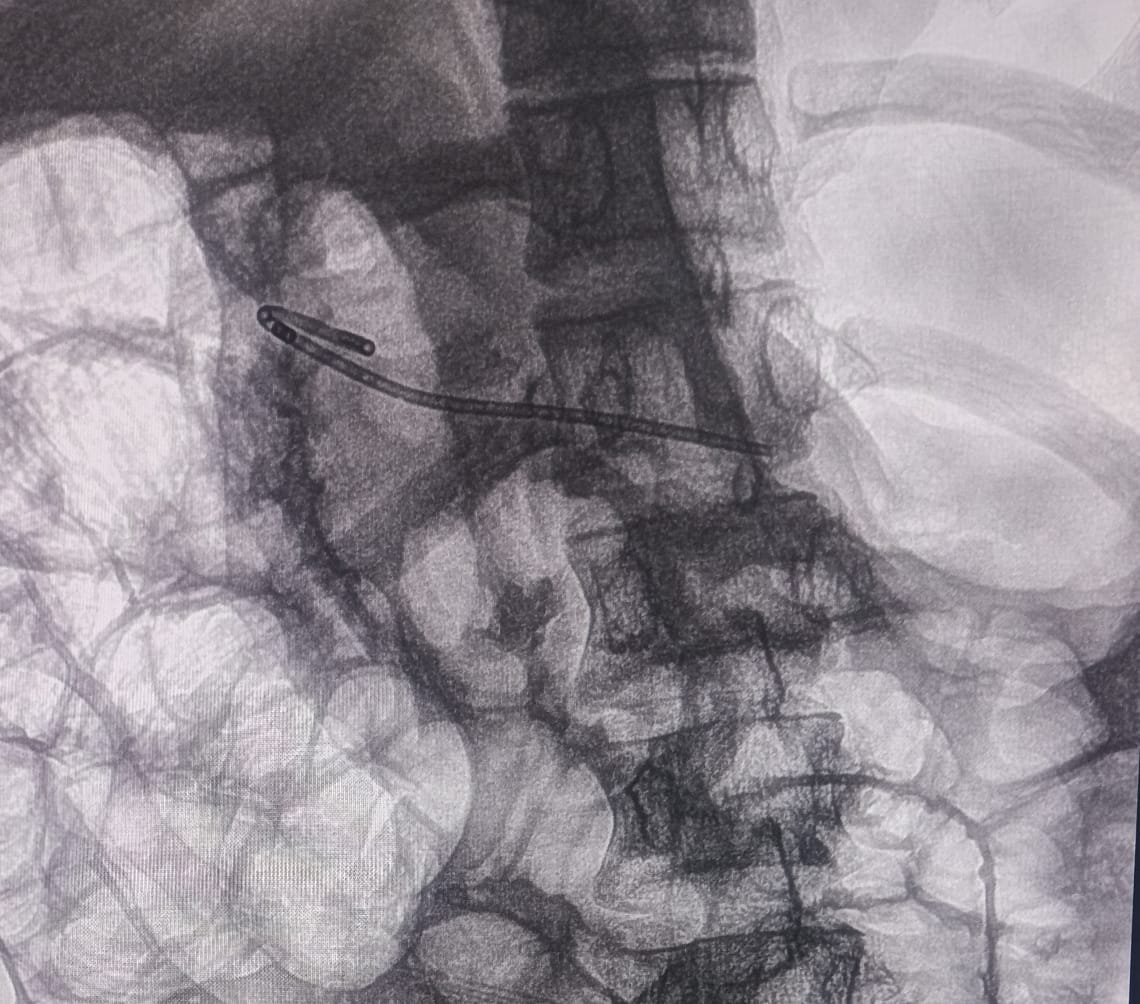

Chronic Pancreatitis ERCP Image 2

Minor Papilla Cannulation

A pinpoint major papilla was noted. PD cannulation was achieved from the minor papilla and dye was injected. The PD was found to be dilated in body and tail up to 5.6mm.

Communication of duct of Santorini was found to be of very small caliber. Cannula was passed into the pancreatic duct of body and tail. Duct of Santorini was dilated up to 4mm with biliary hurricane balloon. A 7Fr x 7cm single pigtail pancreatic stent was placed in the PD.